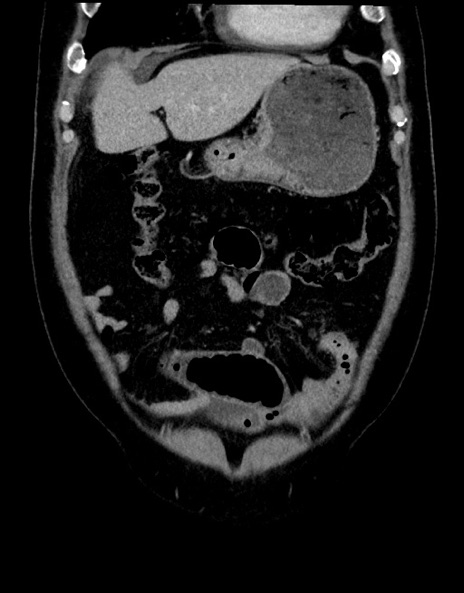

横断像

【症例】70歳代男性

【主訴】腹痛

【現病歴】今朝から腹痛あり。全体的に痛い。特に左上の方。排ガスが今日はない。冷や汗が出る。

【既往歴】直腸癌術後

【身体所見】左側腹部〜上腹部に圧痛あり。腹膜刺激症状明らかなではない。軽度反跳痛。左下腹部に術後瘢痕あり。

【データ】WBC 7700、CRP 0.02